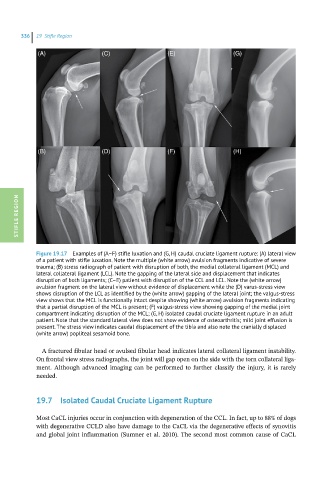

Figure 19.17 Examples of (A–F) stifle luxation and (G, H) caudal cruciate ligament rupture: (A) lateral view

of a patient with stifle luxation. Note the multiple (white arrow) avulsion fragments indicative of severe

trauma; (B) stress radiograph of patient with disruption of both, the medial collateral ligament (MCL) and

lateral collateral ligament (LCL). Note the gapping of the lateral side and displacement that indicates

disruption of both ligaments; (C–E) patient with disruption of the CCL and LCL. Note the (white arrow)

avulsion fragment on the lateral view without evidence of displacement while the (D) varus-stress view

shows disruption of the LCL as identified by the (white arrow) gapping of the lateral joint; the valgus-stress

view shows that the MCL is functionally intact despite showing (white arrow) avulsion fragments indicating

that a partial disruption of the MCL is present; (F) valgus-stress view showing gapping of the medial joint

compartment indicating disruption of the MCL; (G, H) isolated caudal cruciate ligament rupture in an adult

patient. Note that the standard lateral view does not show evidence of osteoarthritis; mild joint effusion is

present. The stress view indicates caudal displacement of the tibia and also note the cranially displaced

(white arrow) popliteal sesamoid bone.

A fractured fibular head or avulsed fibular head indicates lateral collateral ligament instability.

On frontal view stress radiographs, the joint will gap open on the side with the torn collateral liga-

ment. Although advanced imaging can be performed to further classify the injury, it is rarely

needed.